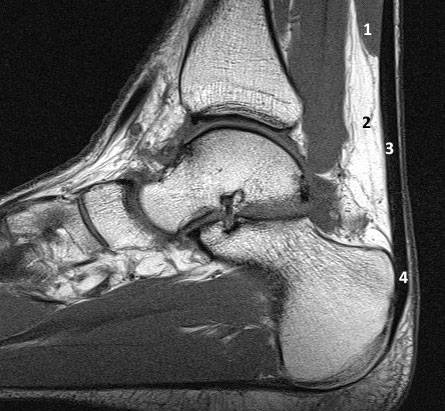

МР-анатомия ахиллова сухожилия

- Мышечно-сухожильная часть

- Жировое тело Кагера

- Неинсерционная часть ахиллова сухожилия

- Инсерционная часть ахиллова сухожилия